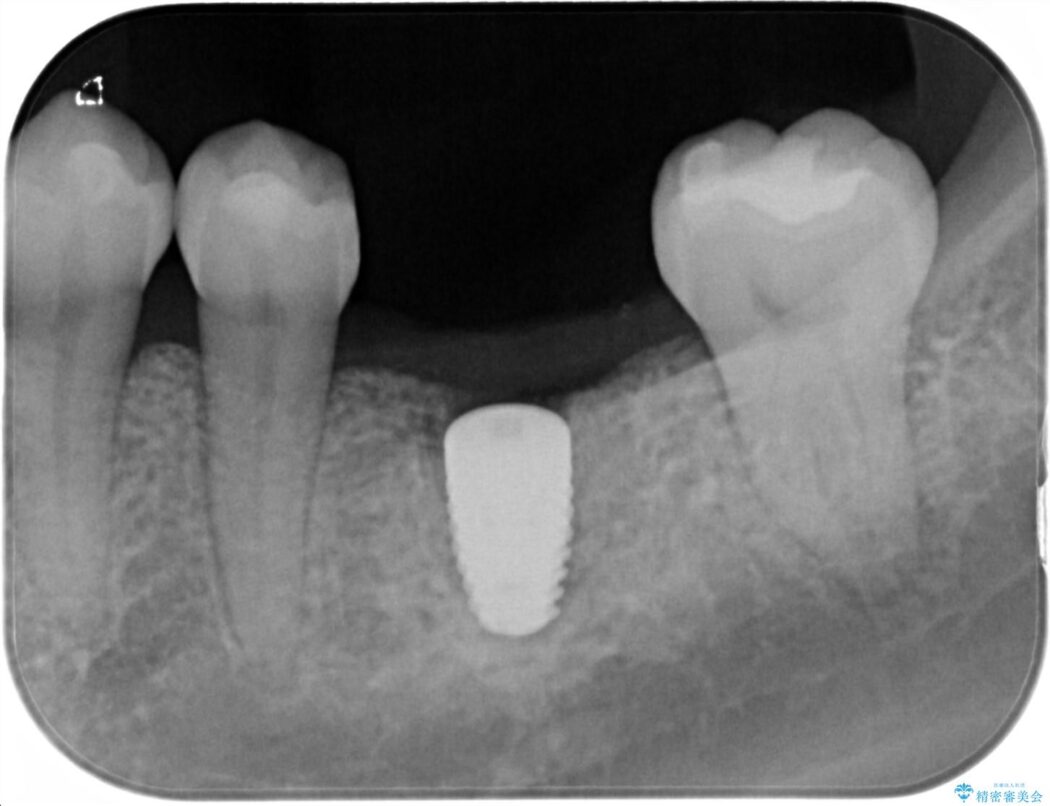

治療計画を立てる上で詳しく精密検査をしたところ、左下の6番目の歯につきまして治療が必要な状態であることが分かり、かぶせ物を外し、内部を確認しました。

結果としては深い部分で根が破折してしまっていました。

破折の処置としては基本的に抜歯が選ばれます。